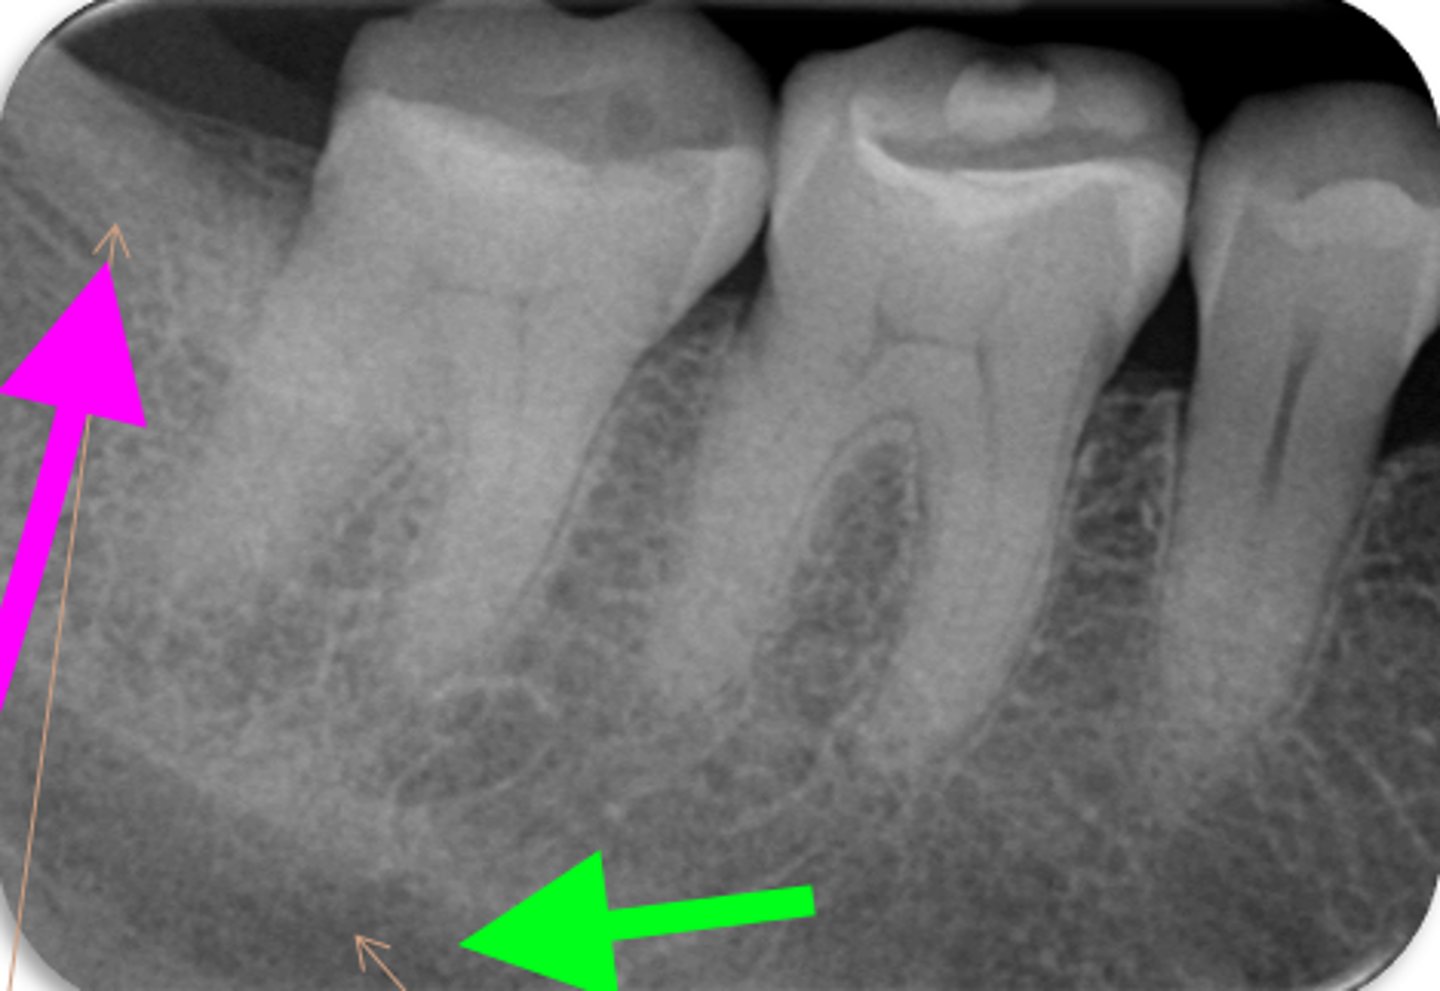

vertical root fracture

ID the problem:

- May not show on PA radiographs

Presents with signs of:

- J-shaped lesion/lateral radiolucency

- Isolated deep pocket

- Coronally located swelling or sinus tract